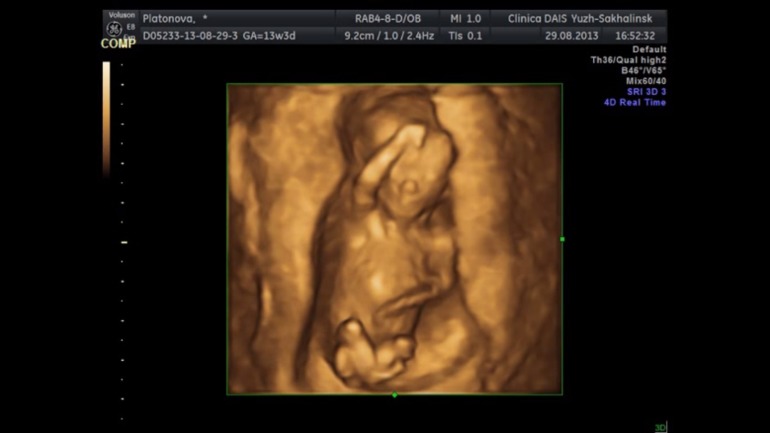

Пол ребенка на узи ошибки

Пол ребенка на узи ошибки 113 фото